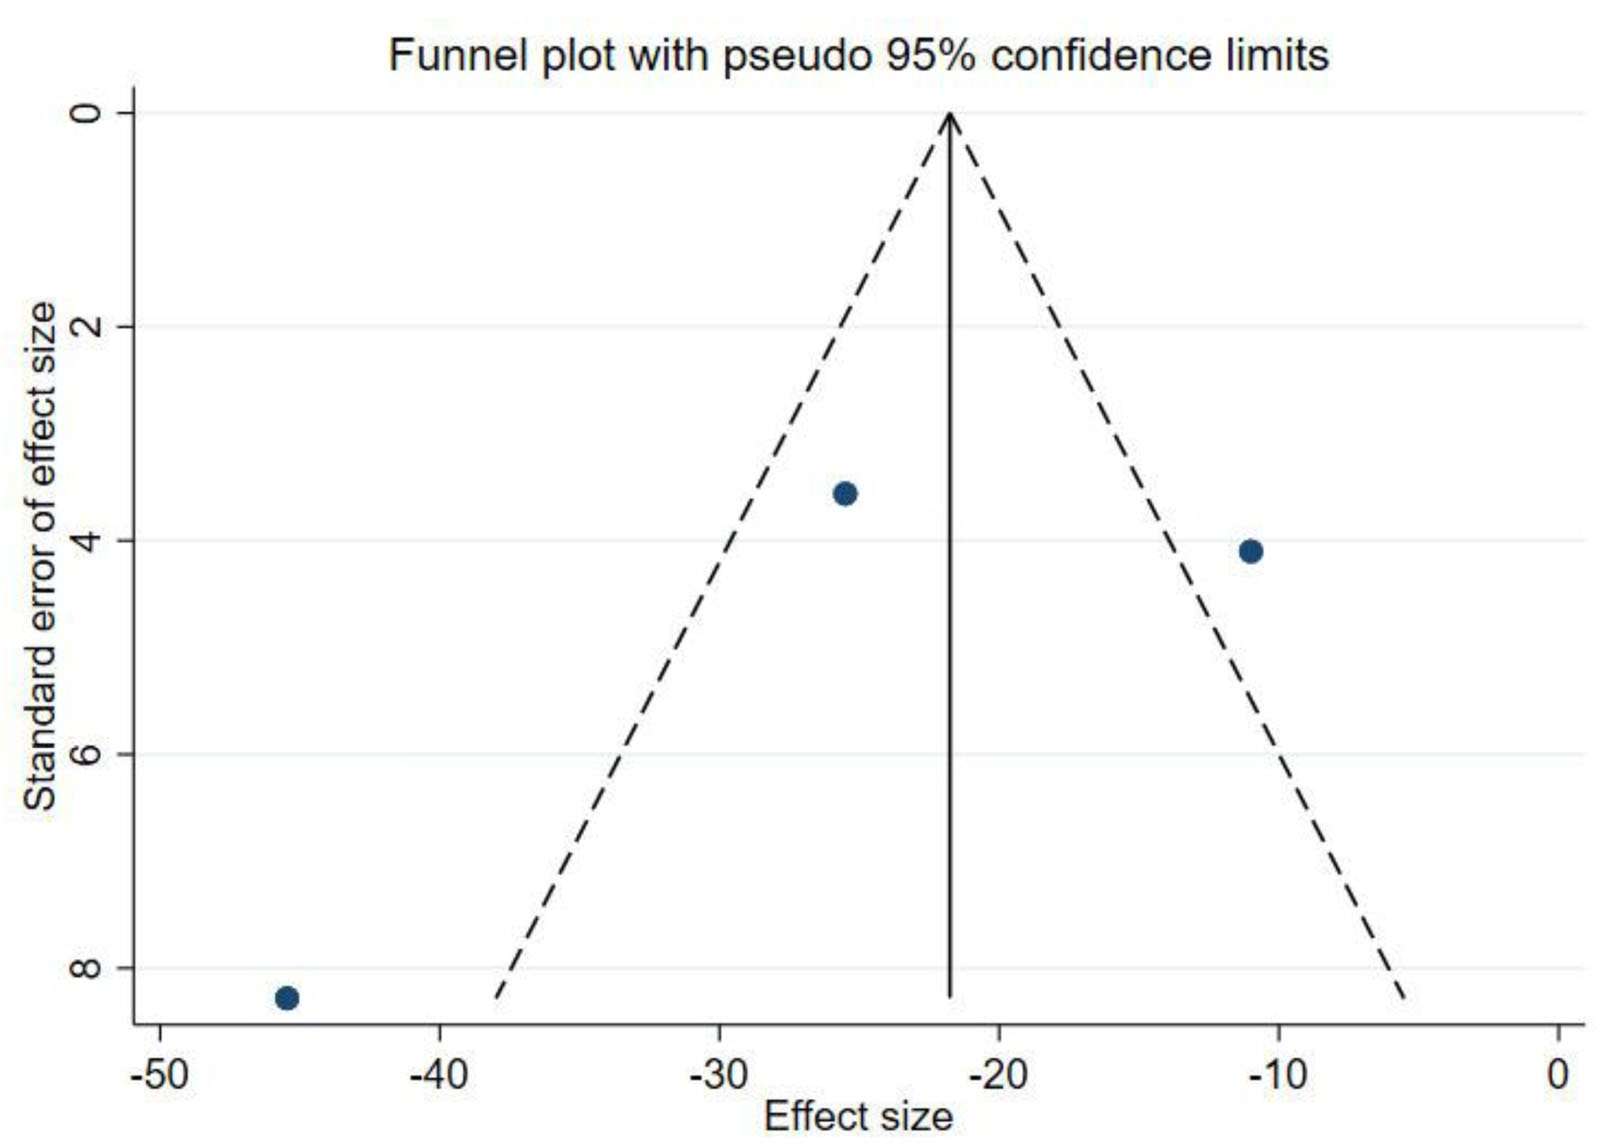

出版偏見:對(duì)納入研究進(jìn)行了發(fā)表偏倚分析,漏斗圖顯示W(wǎng)OMAC不對(duì)稱,而KLS對(duì)稱,提示W(wǎng)OMAC結(jié)果可能存在發(fā)表偏倚(圖4、圖5),因此進(jìn)行了Egger檢驗(yàn),結(jié)果顯示P=0.583,提示不存在發(fā)表偏倚(圖6)。

WOMAC=西安大略和麥克馬斯特大學(xué)骨關(guān)節(jié)炎指數(shù)。